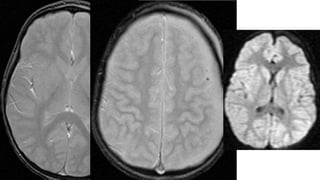

Este documento presenta el caso de un niño de 3 años que sufrió episodios de paresia y alteraciones neurológicas. Exámenes revelaron la presencia de un higroma cerebral que fue drenado. A pesar de una mejoría inicial, el niño continuó presentando síntomas neurológicos intermitentes. Exámenes posteriores identificaron una rara vasculopatía que afecta vasos cerebrales y otros órganos, con un pronóstico grave.